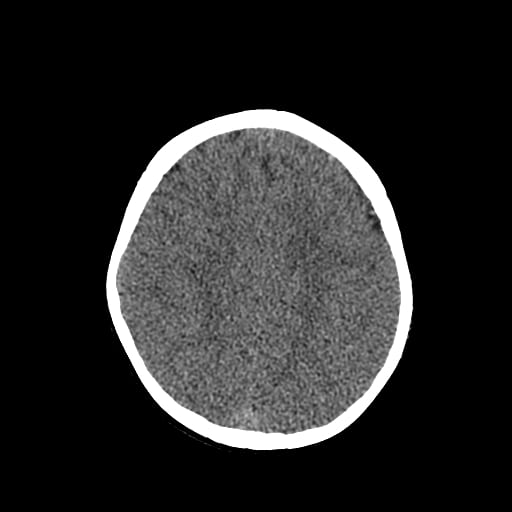

Age: 1

Sex: Male

Indication: Fall